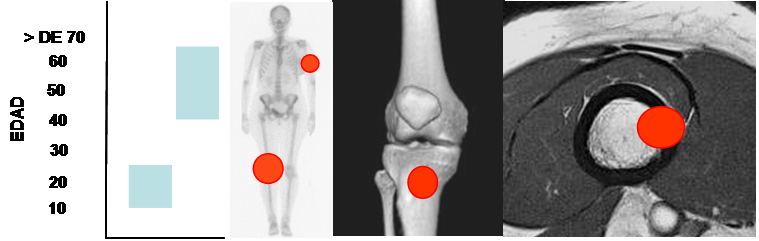

Fig 68. Osteosarcoma.

Dos picos de aparición entre la 2º y 3º décadas y después de los 40 años. Predominio en los huesos largos. Lesión metafisiaria, de ubicación excéntrica y cortical.